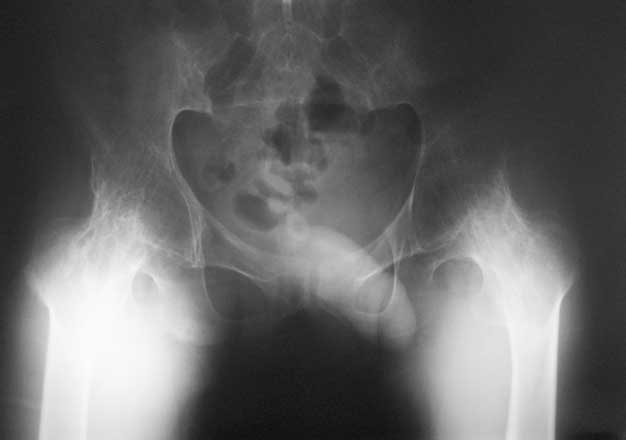

Уважаемые коллеги, в отделении находится пациент 28 лет, страдающий ревматоидным артритом с детства. В настоящее время основной проблемой для него являются тазобедренные суставы - костный анкилоз в положении сгибания около 80 град.

Выраженная атрофия мышц. ограничение движений в коленных суставах.Суставы "замкнулись" со слов пациента около 5 лет назад. Пациент работает (сидячая работа, высшее образование). Все проблемы перечислять не буду. Основное -сложности с ходьбой,самообслуживанием, эстетика и т.д.

1. Насколько возможно и целесообразно эндопротезтрование в такой ситуации?

Наш план - остеотомия на уровне шейки бедра, иссечение капсулы, субспинальная тенотомия, а так же приводящих мышц, фасции, после чего - дозированное разгибание АВФ "таз -бедро".

Насколько это реально. кто-нибудь имел подобные случаи, возможно ли разогнуть бедро без неврологии, другие варианты релиза?